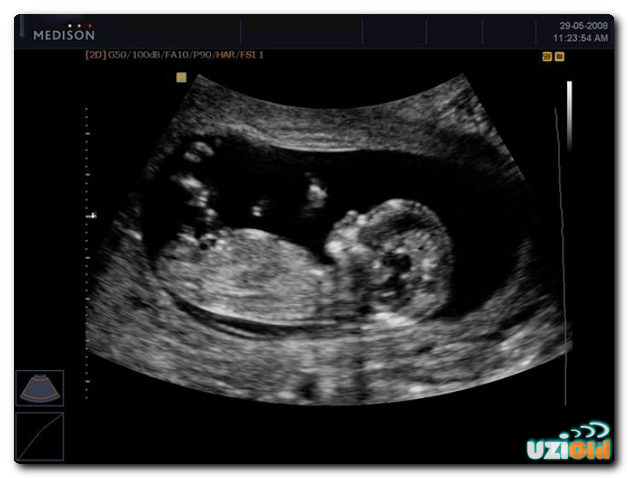

Пренатальное ежедневное развитие ребёнка: